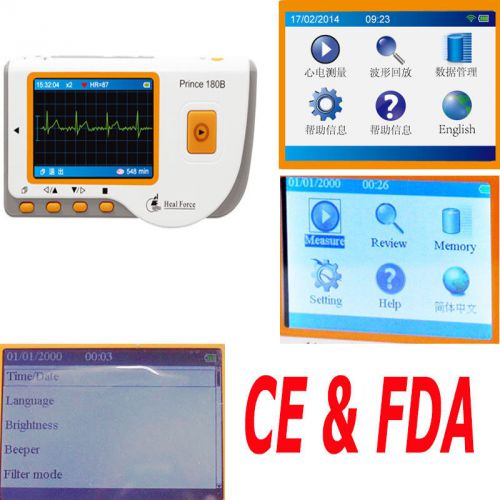

2015 FDA Heal force Color LCD 80B Handheld Portable ECG Monitor EKG Machine +USB

Hot!Prince 180B Handheld Electrocardiogram portable ECG EKG Monitor LCD+USB